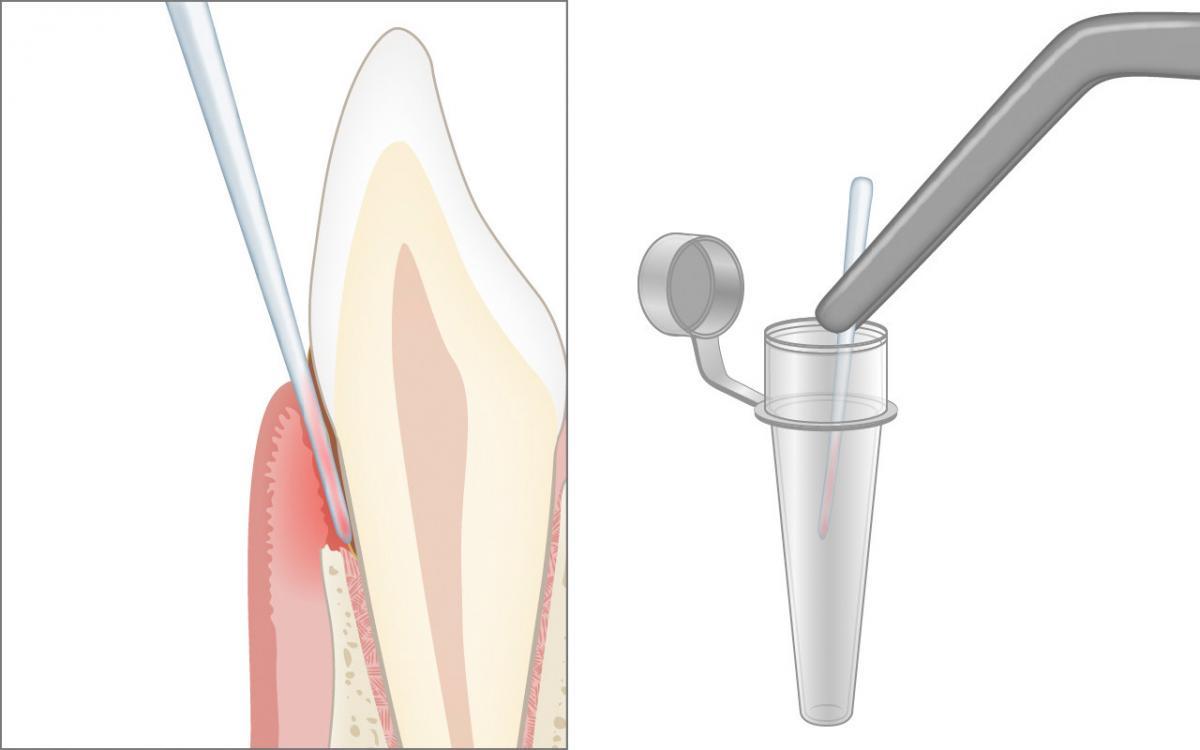

Mehr …Die millimetergenaue klinische Sondierung mit der Zahnfleischsonde zur Ausmessung der Zahnfleischtaschen und der Höhe des Kieferknochens sind zur Diagnose der Parodontitis unverzichtbar.

Erst die korrekte klinische Untersuchung in der Zahnarztpraxis mit einer sogenannten Zahnfleischsonde (Parodontalsonde) kann Aufschluss geben, ob das Zahnfleisch gesund ist, eine Zahnfleischentzündung (Gingivitis) oder bereits eine Erkrankung der Zahnverankerung (Parodontitis) vorliegt.

Mit einer Zahnfleischsonde (Parodontalsonde) wird an ausgewählten Stellen schonungsvoll und millimetergenau die Eindringtiefe am Zahnfleischrand gemessen.

Die millimetergenaue klinische Sondierung mit der Zahnfleischsonde zur Ausmessung der Zahnfleischtaschen und der Höhe des Kieferknochens sind zur Diagnose der Parodontitis unverzichtbar.